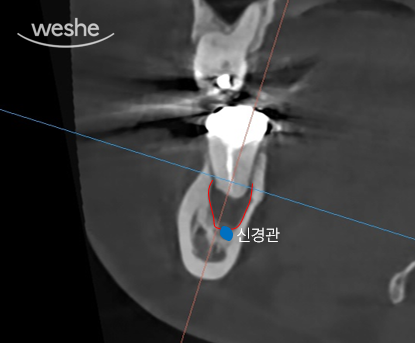

빨간색으로 보이는 부분은 염증으로 인해 뼈가 녹아 있는 부위,

파란색은 턱과 치아의 감각을 담당하는 하치조 신경입니다.

보시는 것처럼 염증이 신경과 맞닿아 있네요.

이대로 시간이 조금 더 지나면

환자분의 오른쪽 아래턱에 감각이상이 생길 수 있습니다.

즉, 감각이 둔해지거나 무뎌지는 증상이 나타날 수 있다는 뜻이지요.

해당 치아는 신경관의 구조가 매우 복잡해

기존 신경치료의 성공률도 높지 않아 보이는데,

재신경치료는 그 성공률이 더 낮아질 수 있기 때문입니다.